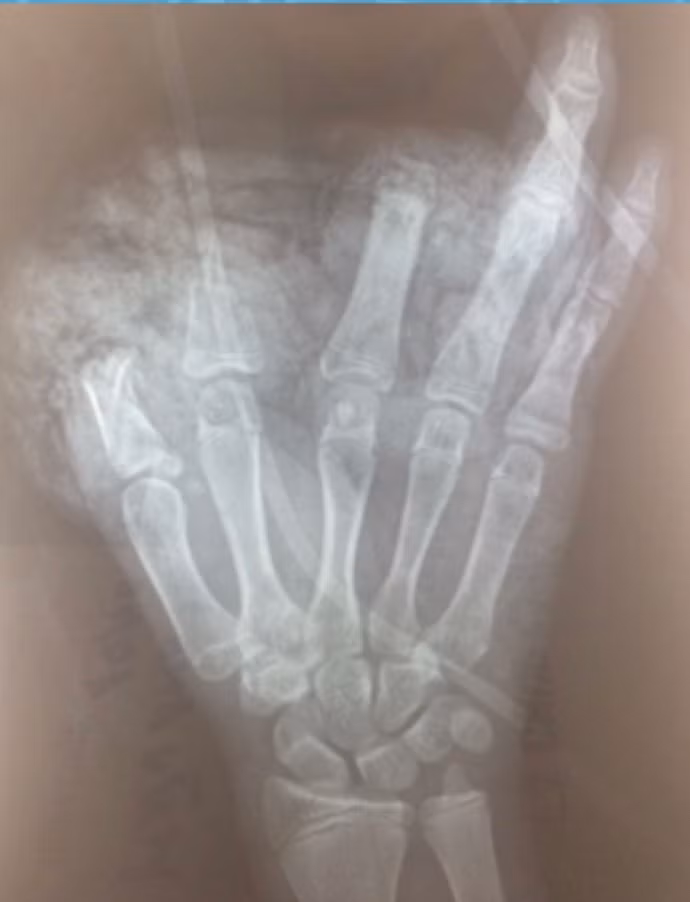

| Hình ảnh X-quang bàn tay trái của bé T. (Ảnh: BVCC) |

Bé N.H.A.T. 14 tuổi, sống ở phường Trang Hạ, Thị xã Từ Sơn, tỉnh Bắc Ninh vào Bệnh viện Hữu nghị Việt Đức trong trạng thái tỉnh, huyết động ổn định, vùng hàm mặt, ngực, bụng có nhiều xây xát; mắt trái bị rách lớp mi trên, cương tụ kết mạc. Không chỉ vậy, bàn tay trái của bé bị dập nát, cụt chấn thương ngón 1,2,3; vết thương mu tay và gan tay dài 10cm, da gan tay bị lóc cùng nhiều dị vật đen, bẩn.

ThS. BS. Đoàn Lê Vinh - Khoa Phẫu thuật Chấn thương Chung, Bệnh viện Hữu nghị Việt Đức - cho biết: Ngay sau khi tiếp nhận bệnh nhi, các bác sĩ đã tiến hành bơm rửa, làm sạch vết thương nhiều lần, cắt lọc sạch vết thương cho bé. Bé đã được được phẫu thuật cấp cứu cắt lọc sửa mỏm cụt ngón 1,2,3; xử lý vết thương phần mềm gan bàn tay, mu bàn tay và nhiều vị trí thương tổn khác. Ca phẫu thuật diễn ra trong 1 tiếng.